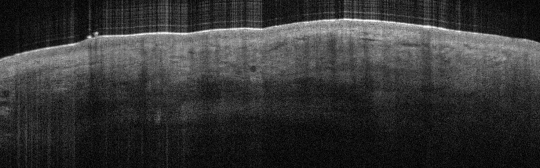

VA9: Left Forearm, Adjacent Normal